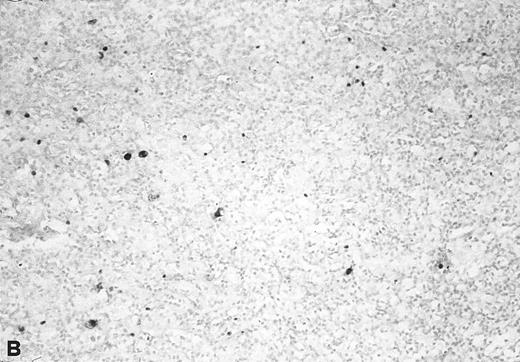

The relative amount of EBV DNA in the EBV+ samples was estimated by comparing the OD values of their amplified EBNA2 products to the OD values obtained using standard reference samples, as detailed in Materials and Methods. As shown in Table 3, most of the EBV+ lymphadenopathy samples had very low levels of EBV DNA (ie, scored either 1+ or 2+) and accordingly, none of the analyzed lymphadenopathy specimens was found to be EBV+ by Southern blot analysis. Three cases were analyzed by in situ hybridization with EBER probes; 1 (no. 20) showed viral sequences in 2% to 3% of cells (Fig 3), and 2 (nos. 21 and 23) were negative. Interestingly, in 4 of 6 coinfected lymphadenopathy cases, the amounts of type 1 and type 2 EBV DNA were equivalent, while either type 1 or 2 predominated in the 2 remaining cases (Table 3).

In situ hybridization with EBER probes. In a representative lymphadenopathy case (no. 20), rare EBER+ cells are seen, mainly in the interfollicular areas (A and B). In a representative lymphoma case (no. 46) nearly half of the cells are EBER+ (C and D). Original magnification: ×130 (A and C) and ×260 (B and D).